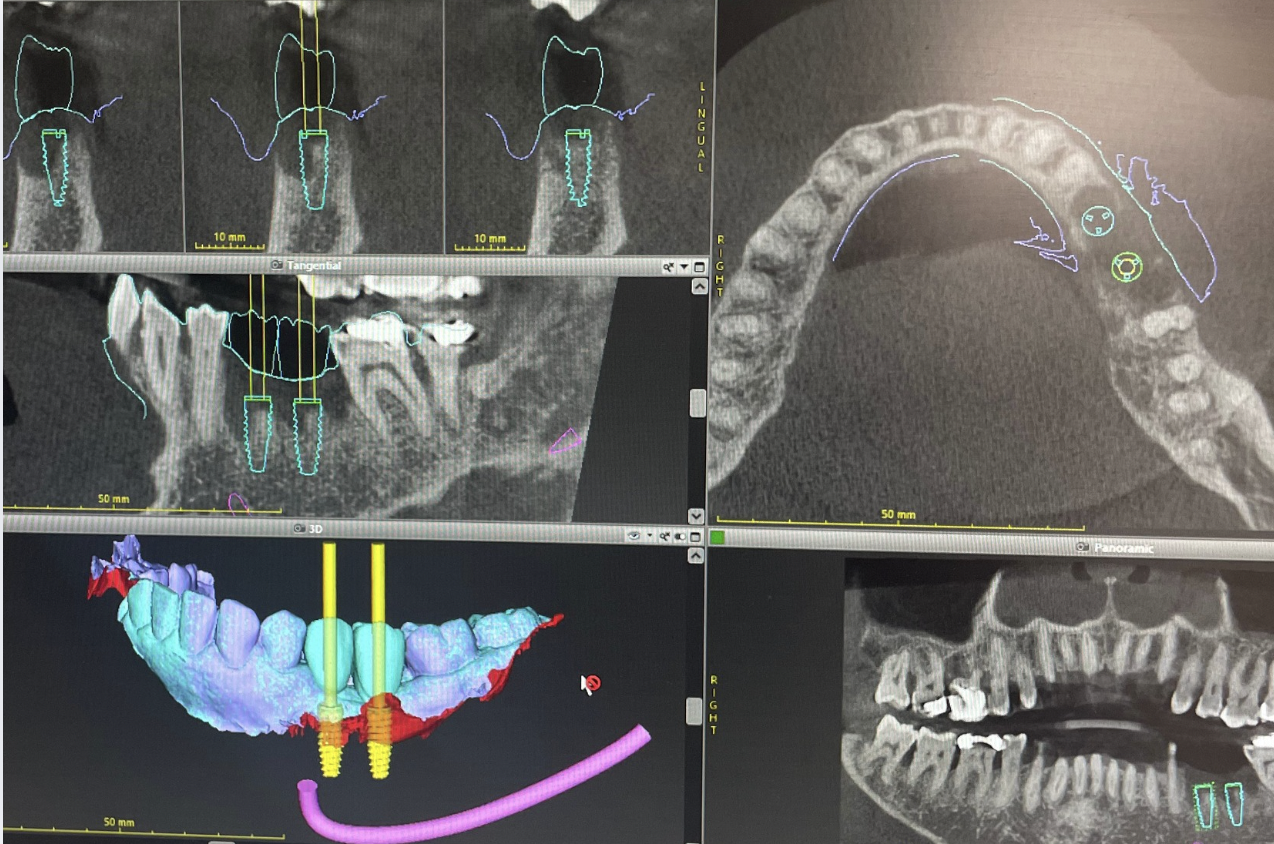

- L’imagerie 3D Cone Beam : Ce scanner permet de reconstituer en trois dimensions l’anatomie du patient, en visualisant avec précision la structure osseuse, les nerfs et les autres éléments importants.

- La planification numérique : Grâce à un logiciel spécialisé, le chirurgien peut simuler l’intervention et déterminer l’emplacement idéal de l’implant, en prenant en compte la morphologie et les contraintes anatomiques.

- Le guide chirurgical : Ce dispositif sur mesure, fabriqué par impression 3D, est placé sur la mâchoire du patient pendant l’intervention. Il sert de repère précis pour insérer l’implant à l’endroit exact prévu lors de la planification.